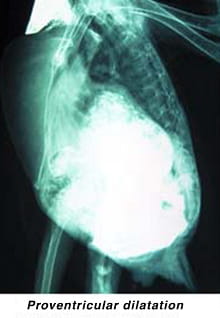

- Macaws were the first species to develop an ultimately fatal disease, proventricular dilatation syndrome, which causes chronic and progressive weight loss, regurgitation, and in some birds, ultimately death. This syndrome is believed to be an autoimmune disease associated with a viral infection called bornavirus. No one yet understands the complete cause of disease, as many bird species are infected with bornavirus and are not clinically affected.